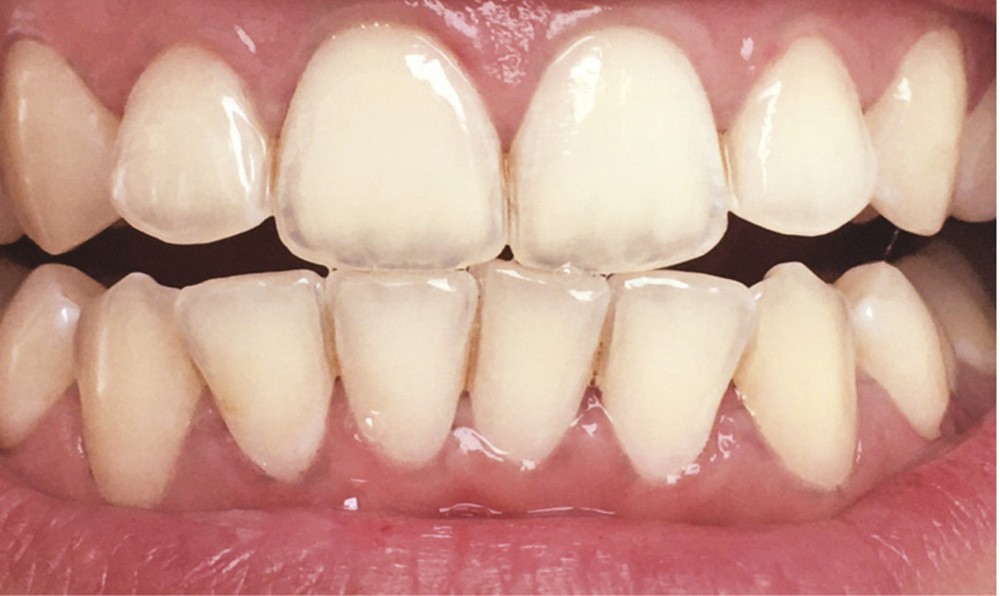

Avoir des dents parfaitement blanches est aujourd’hui synonyme de beauté, de jeunesse, de séduction, de santé, et véhicule également l’idée de réussite sociale. De nombreuses techniques existent en dentisterie pour améliorer l’esthétique dentaire : détartrage-polissage, aéropolissage, blanchiment interne ou externe, facettes… Cependant, les patients, et principalement les jeunes patients, souvent refroidis par le prix d’un blanchiment dentaire, réputé coûteux, se tournent facilement vers des « recettes de grand-mère » ou certains produits très populaires actuellement. Leurs effets miracles sont largement relayés par les publicités, de nombreux sites internet et les réseaux sociaux. Si l’utilisation de ces remèdes est difficilement chiffrable du fait de leur usage domestique, près de 40 % des Français y auraient recours. Hormis les avantages économiques, les patients y voient également un avantage écologique relatif à l’utilisation de produits « naturels », « sans risques » permettant de préserver la planète…